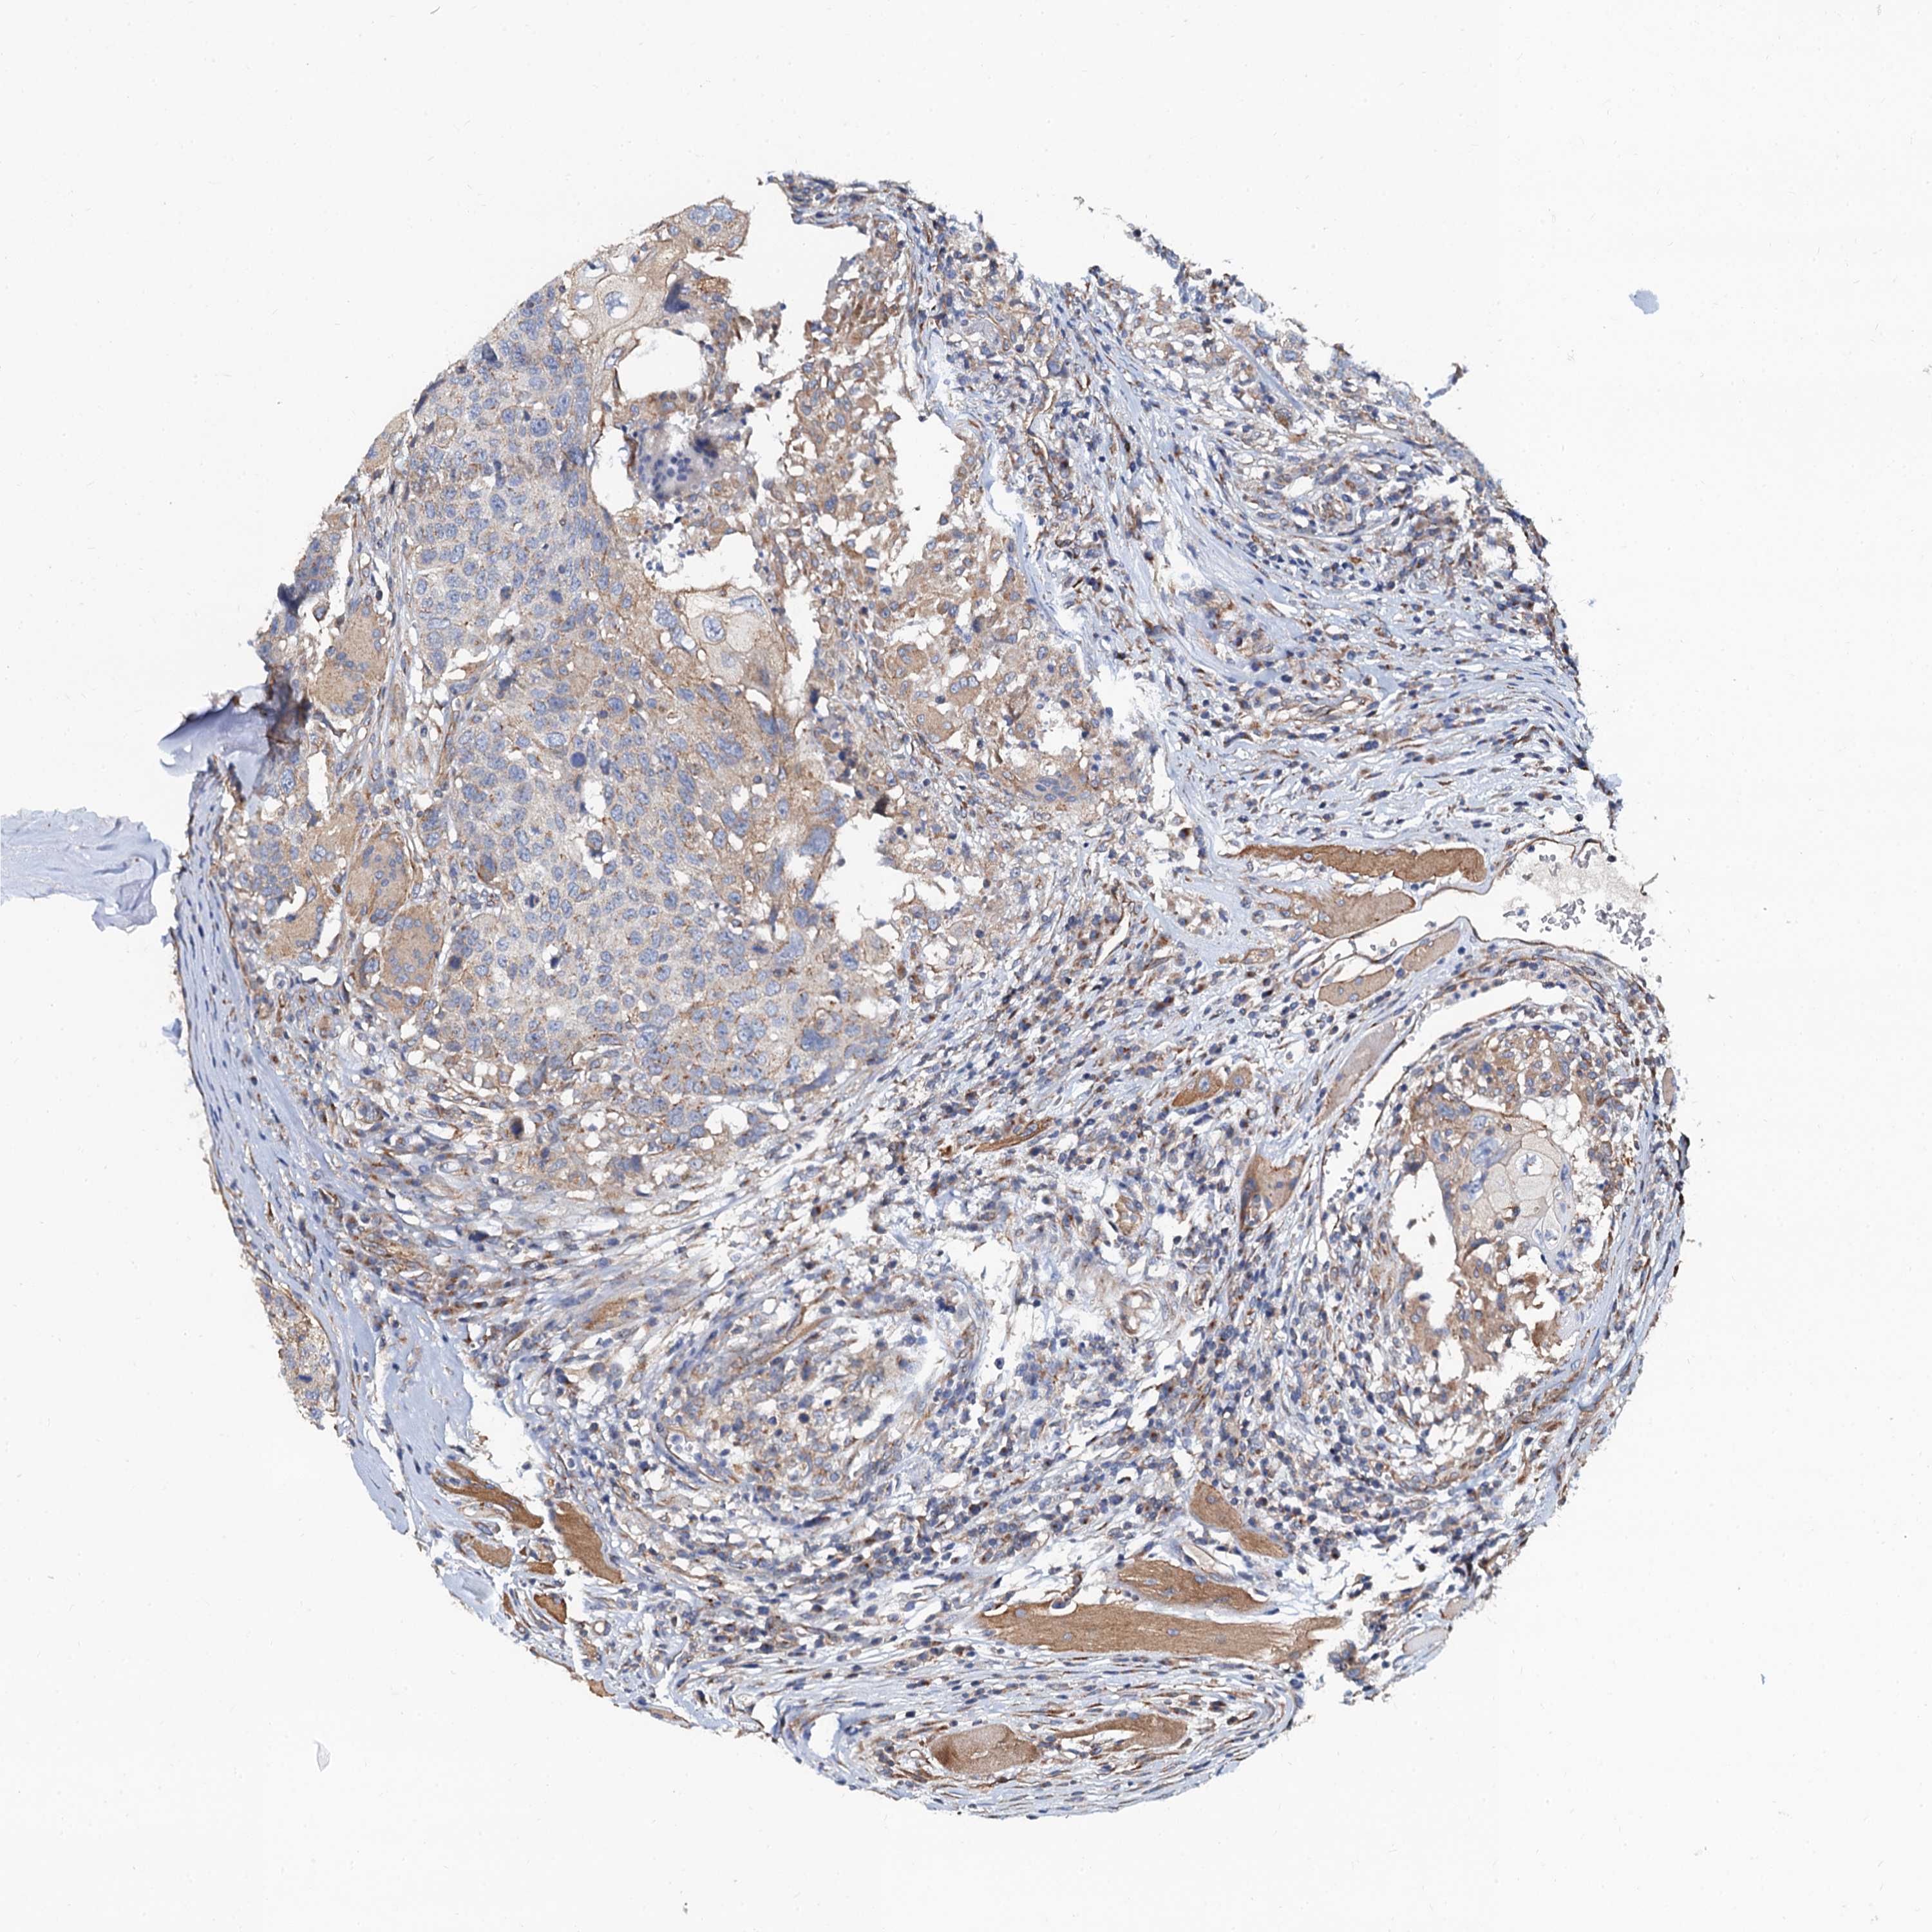

HEAD AND NECK CANCER - Protein expressioni

A mouse-over function shows sample information and annotation data. Click on an image to view it in a full screen mode. Samples can be filtered based on level of antibody staining by selecting one or several of the following categories: high, medium, low and not detected. The assay and annotation is described here.

Antibody stainingi

Antibody staining in the annotated cell types in the current human tissue is reported as not detected, low, medium, or high, based on conventional immunohistochemistry profiling in selected tissues. This score is based on the combination of the staining intensity and fraction of stained cells.

Each image is clickable and will lead to virtual microscopy that enables deeper exploration of all samples and also displays staining intensity scores, fraction scores and subcellular localization as well as patient and tissue information for each sample.

Antibody HPA041367

Staining

High

Medium

Low

Not detected

Intensity

Strong

Moderate

Weak

Negative

Quantity

>75%

75%-25%

<25%

None

Location

Nuclear

Cytoplasmic/membranous

Cytoplasmic/membranous,nuclear

Squamous cell carcinoma, metastatic, NOS